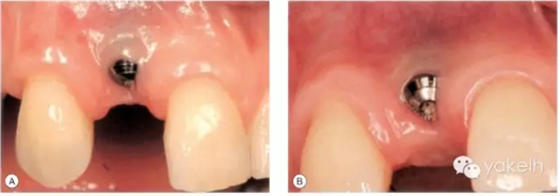

病例5

患者先天缺失側(cè)切牙,同時(shí)由于外傷UR1缺失。UR1種植修復(fù)。該種植冠大約有2mm 的牙齦退縮,與UL1相比,該修復(fù)冠較長(圖.8A)。這是由于種植體植入位置過深而導(dǎo)致的(圖.8B)。

圖.8 種植體植入過深,引起牙齦退縮以及修復(fù)冠過長。